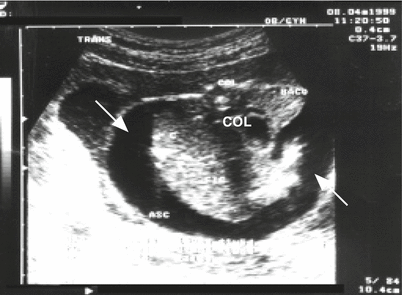

Fig. 15.13

Congenital toxoplasmosis coursing with fetal hydrops. Cross-section of the fetal abdomen at the level of the liver with an anechoic image and ascites (arrow). COL column, ASC ascites